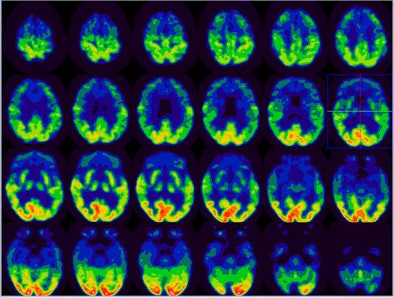

![]() |

| In this image of frontotemporal dementia, there is severely reduced FDG activity in the bilateral anterior temporal, bilateral frontal, and bilateral anterior parietal regions. Mild to moderate to decreased FDG uptake is most noted in mid to posterior temporal and regions. This finding is consistent with frontotemporal dementia. All images courtesy of Dr. Roland Talanow and the Cleveland Clinic. |